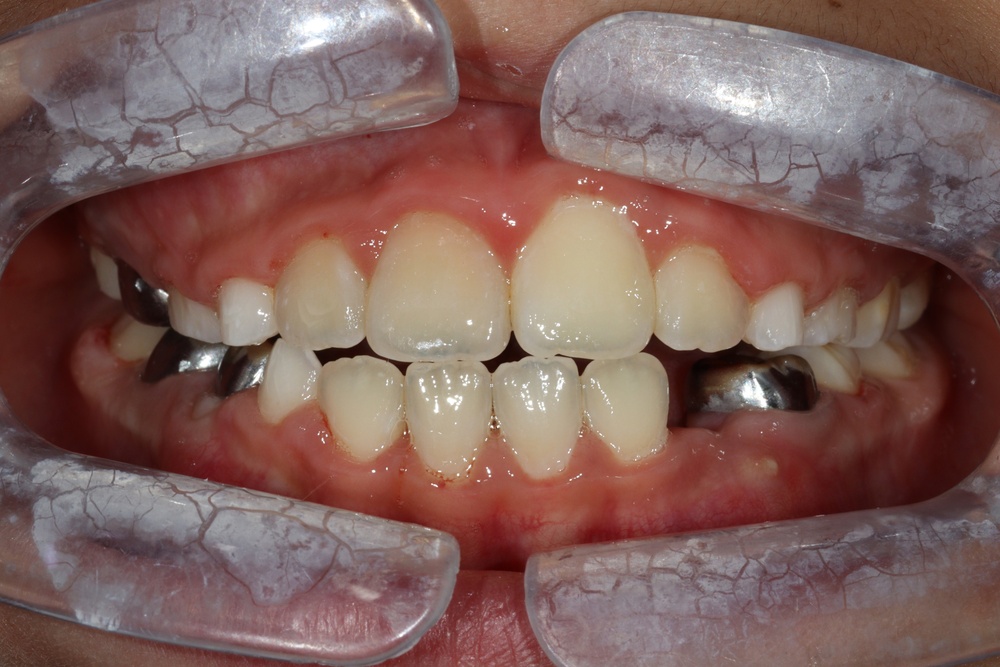

치아 배열이 거의 완성된 상태로 치료 전 말씀드렸던 치아사이의 틈(블랙트라이앵글)이 있습니다.

환자분과 상의 후 위쪽은 벌어진 공간을 레진으로 메꾸기로 하였습니다.

치아가 가지런해졌고, 윗니 치아 사이의 틈도 메꿔졌으며, 치아에 있던 충치도 모두 치료하였습니다.